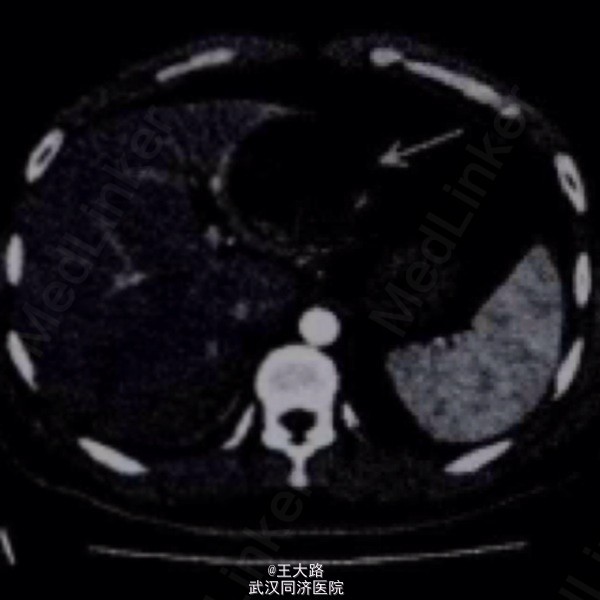

肝囊肿ct图片影像

肝囊肿ct图片影像,肝囊肿影像学图片

ct检查女性,55岁,ct体检提示左肝囊肿,无明显不适.入院诊断病例一